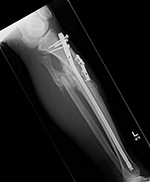

| 36 year-old man with bullet wound in 2003 complicated by femur fracture infected non-union treated by multiple attempts with external fixation and open reduction and internal fixation (ORIF). Radiography 12 years later shows chronic fracture hypertrophic nonunion, multiple shrapnel fragments, and breakage of a periarticular fixation plate. |